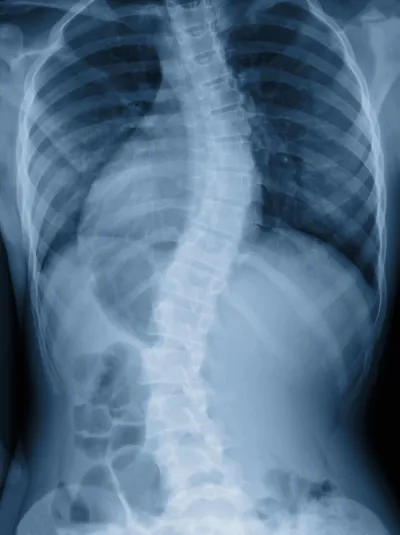

Skoliosebehandlung nach Schroth

Mit der Schroth-Methode behandeln wir Skoliosen und Haltungsschwächen dreidimensional: durch gezielte Kräftigung, Dehnung und spezielles Atemtraining. Ziel ist es, die Verkrümmung zu verlangsamen oder langfristig zu verbessern – damit Sie aufrechter durchs Leben gehen.

Die Skoliosebehandlung nach Schroth ist eine physiotherapeutische Methode, in der die Skoliose in drei bis vier Krümmungen bzw. Körperblöcke eingeteilt wird.

Durch gezielte Kräftigungs- und Dehnungsübungen kombiniert mit spezifischem Atemtraining versucht man die verschiedenen Körperabschnitte wieder in eine möglichst physiologische Form zu bringen und dadurch die Krümmungszunahme der Wirbelsäule bewusst zu verlangsamen bzw. im idealen Fall langfristig zu verbessern.

Skoliosen mit einem Winkel bis 20° werden physiotherapeutisch behandelt. Ab einem Cobb Winkel von über 20° Grad wird zusätzlich ein Korsett verordnet. Bei sehr stark ausgeprägten Skoliosen (Cobb Winkel von 40-60°) sollte eine wirbelsäulenversteifende Operation in Erwägung gezogen werden.

Neben der dreidimensionalen Behandlung von Skoliosen können auch skoliotische Fehlhaltungen (Cobb Winkel unter 10°) bzw. andere Wirbelsäulenveränderungen mit diesem Konzept behandelt werden: